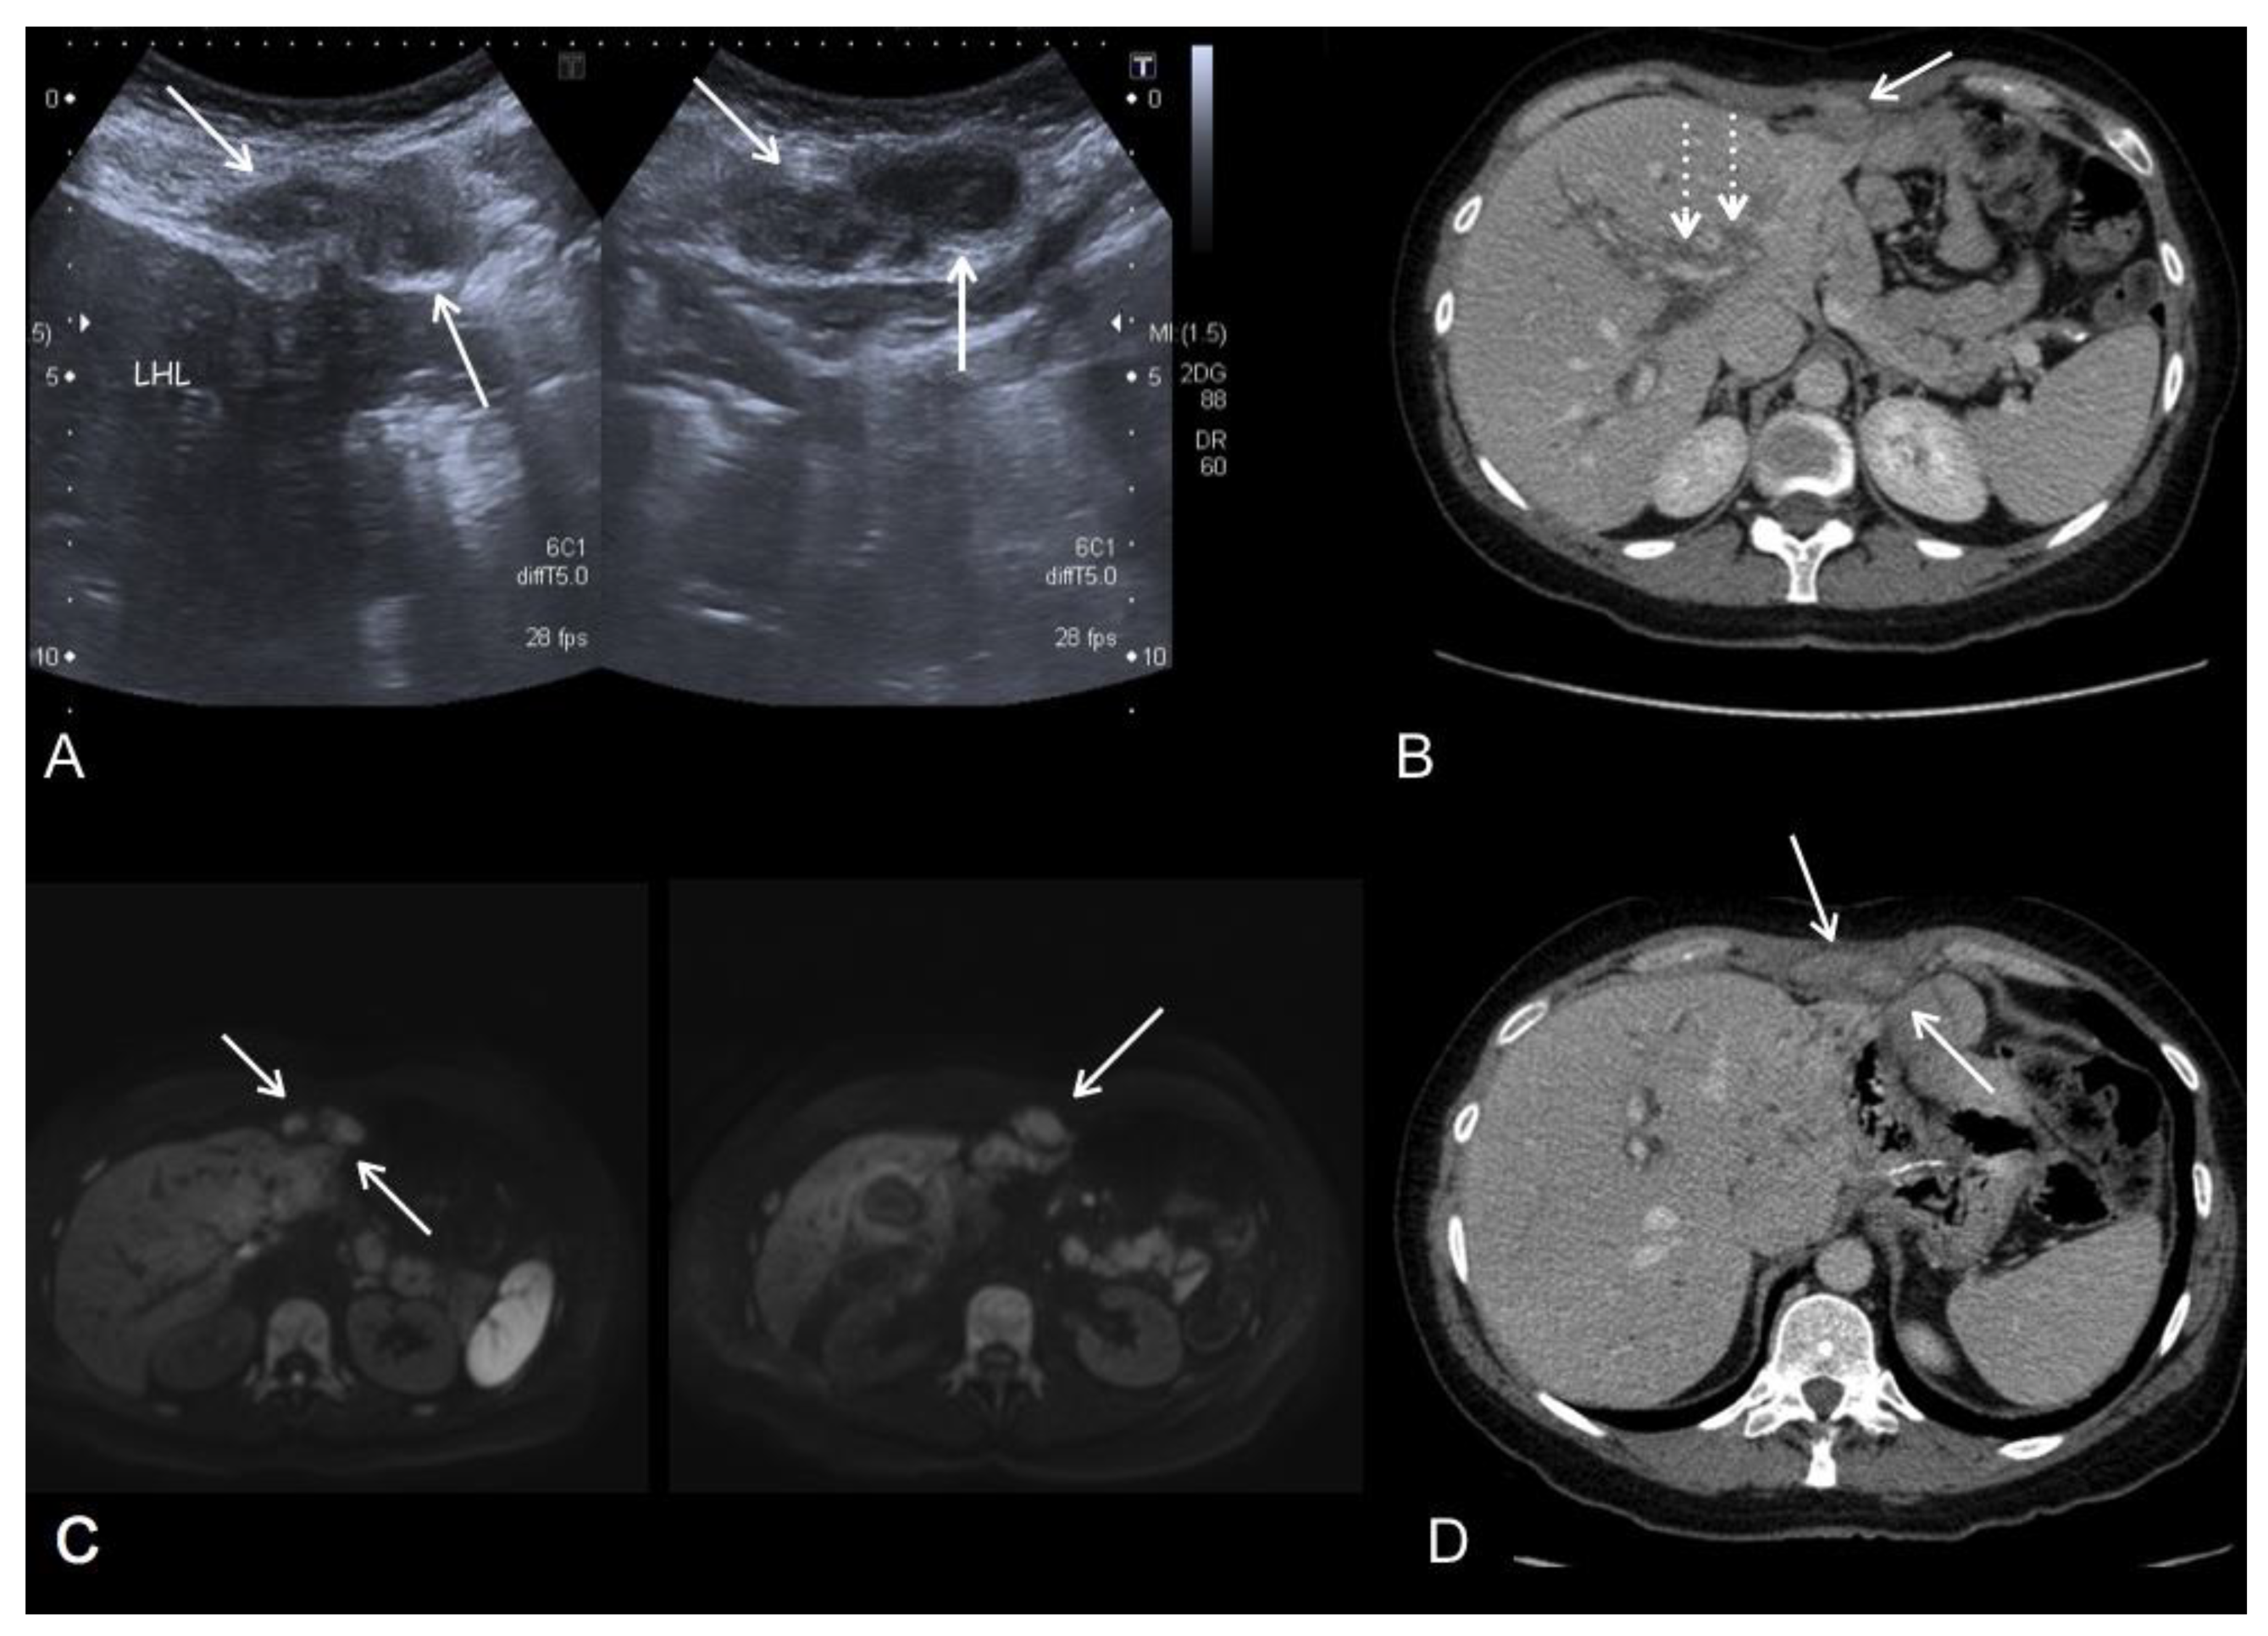

2.2. Magnetic Resonance Imaging (MRI)

- De Vuysere, S.; Vandecaveye, V.; De Bruecker, Y.; Carton, S.; Vermeiren, K.; Tollens, T.; De Keyzer, F.; Dresen, R.C. Accuracy of whole-body diffusion-weighted MRI (WB-DWI/MRI) in diagnosis, staging and follow-up of gastric cancer, in comparison to CT: A pilot study. BMC Med. Imaging 2021, 21, 1–9. [Google Scholar] [CrossRef] [PubMed]